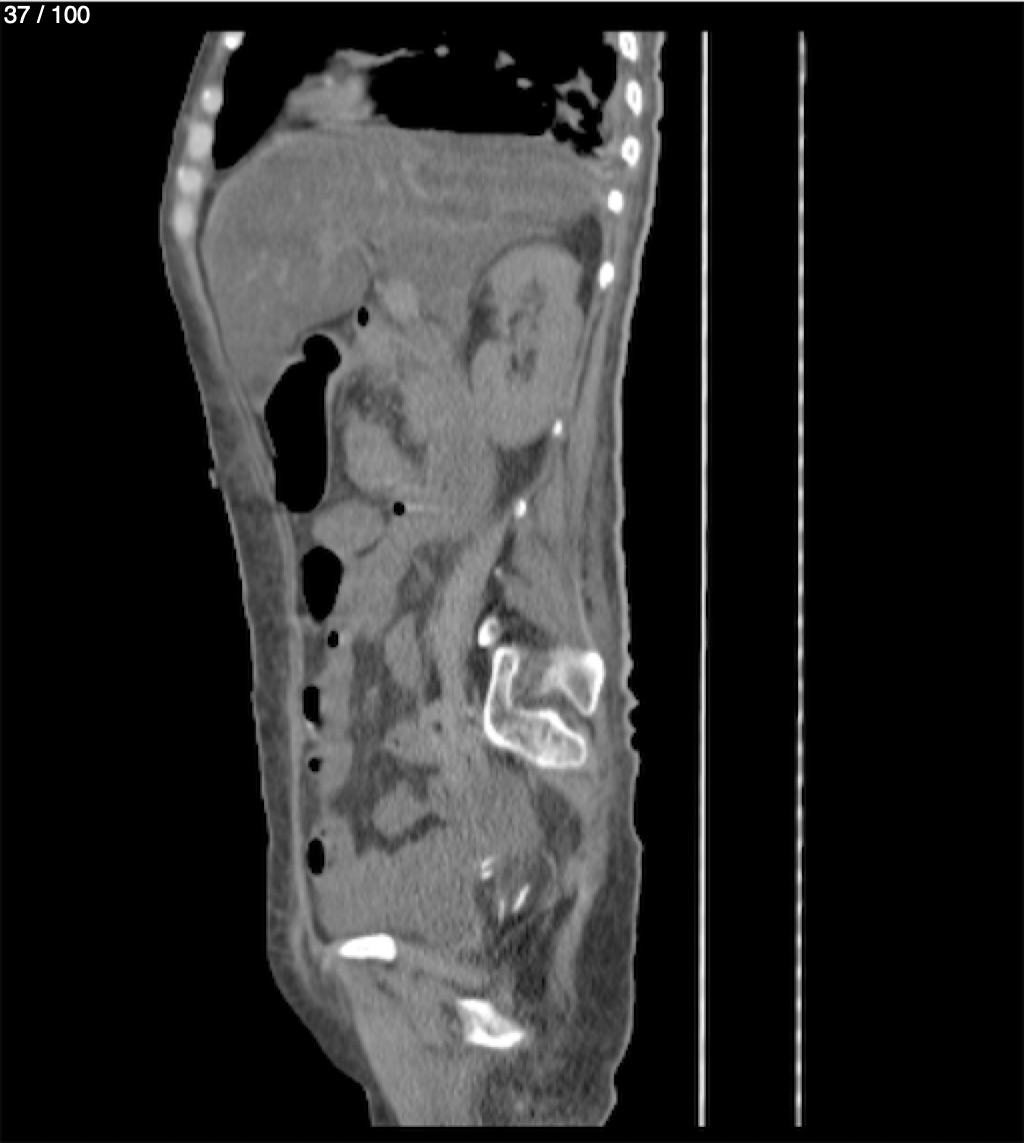

Hilda Geronimo Mendez 60A - T.C Abdomen Simple